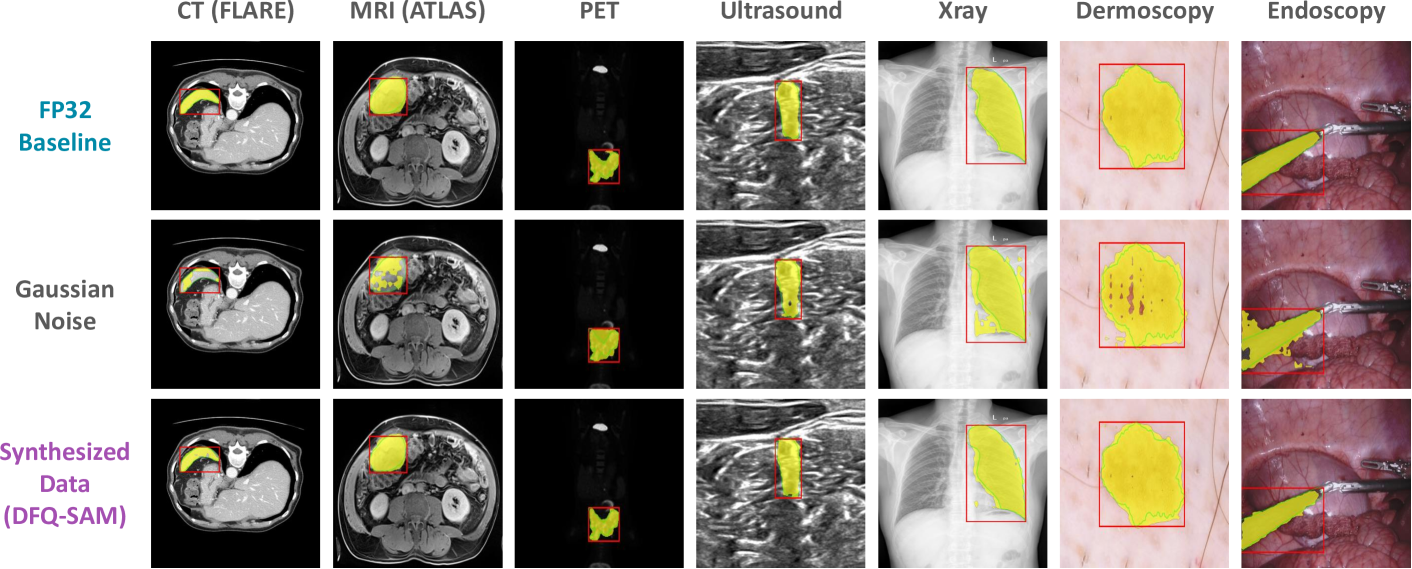

Refer to caption

Figure 3: Visualization of segmentation results on different datasets (256×\times×256 pixels). The proposed DFQ-SAM, which utilizes synthesized data for 4-bit quantization, consistently performs comparable to full-precision baseline. See Fig. 11 for more samples.

Here, we conduct extensive experiments on a variety set of datasets to demonstrate the accuracy advantages of the proposed DFQ-SAM. Notably, to highlight the generalization and robustness of the algorithm, the adopted datasets are from diverse modalities, including CT, MRI, PET, Ultrasound, Xray, Dermoscopy, and Endoscopy. The evaluation metric is the predicted IoU of the masks. The accuracy results are presented and discussed in detail below.